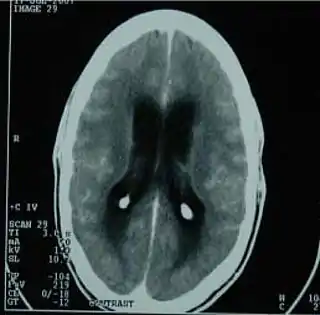

![]() TAC del cerebro mostrando una meningitis tuberculosa. | ||